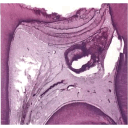

abscesopulpar-2.png